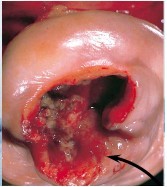

A woman presents to your office for a pap smear after not having one for 10 years. She noticed some bleeding and discomfort with intercourse. Upon exam, you find the following:

Fully invasive carcinomas are exophytic/ ulcerating, and can be keratinizing or non-keratinizing. It can invade adjacent structures (parametrium, bladder, rectum) causing ureter obstrauction and fistula formation. Lymph spread to paracervical, hypogastric, external iliac lymph nodes